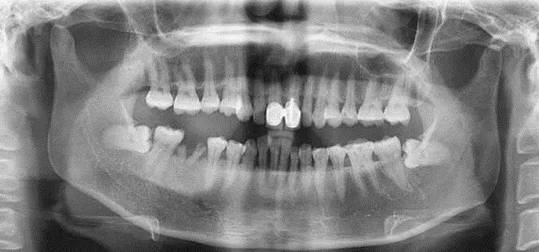

慢性根尖周肉芽肿慢性根尖周肉芽肿是根尖周组织受到轻微的感染刺激后产生的一团炎性肉芽组织。它是慢性根尖周炎的主要病变类型。一般无疼痛症状,有时有咀嚼乏力或不适。患牙多有深龋,牙髓多已坏死,牙齿变色,失去透明度,对冷、热诊及电诊均无反应,叩痛(—),但有时有异样感或叩痛,X线片示:有根尖周的骨质破坏区,即围绕根尖部的圆形或椭圆形边界清楚的透射区。

慢性根尖周脓肿慢性根尖周脓肿是慢性根尖周肉芽肿中央的细胞坏死、液化形成的脓肿;或急性根尖周脓肿处理不彻底,根尖部潴留的脓液被周围纤维结缔组织包绕而形成的。无窦型慢性根尖周脓肿症状与慢性根尖周肉芽肿大致相同,多无自觉症状。有窦型慢性根尖周脓肿患牙根尖部的颊、唇侧可见窦道口,窦道口也可能开口于远离患牙的位置,应仔细检查。X线片示:根尖部边界模糊的透射区,透射区周围骨质也较疏松。

慢性根尖周囊肿慢性根尖周囊肿是由慢性根尖周肉芽肿或慢性根尖周脓肿发展而来的。根尖囊肿生长缓慢,多无自觉症状。牙体可变黄色或深灰色,且无光泽,叩诊可有不适感,对冷、热诊及电诊均无反应;囊肿大小不等,发展较大时,可见根尖部相应软组织膨隆,表面不红,扪压富于弹性,有乒乓球感;囊肿过于肥大时,周围骨质被压迫吸收,可引起牙齿松动,或压迫邻牙使牙根吸收或邻牙移位。X线片示患牙根尖有圆形透射区,边界清楚,周围有白线围绕,此为诊断的重要依据。较小的根尖周囊肿与根尖周肉芽肿不好区分,大的根尖周囊肿应与颌骨囊肿及造釉细胞瘤相鉴别。